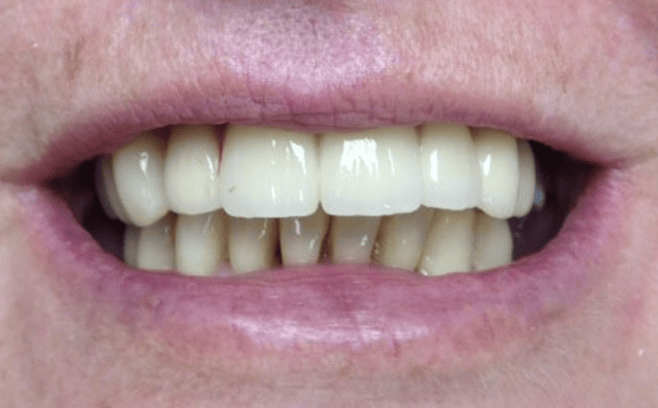

Remplacement de dents pour un sourire durable

Au Cabinet Dentaire Les Dauphins, situé à Baie-Mahault en Guadeloupe, nous sommes spécialisés en implantologie dentaire, pour offrir à chaque patient un sourire durable et harmonieux.

Grâce à notre expertise en implantologie, parodontologie et dentisterie esthétique, nous remettons en œuvre la structure de la dentition en adoptant une approche personnalisée, performante et respectueuse.

L’empreinte, la couleur, la forme sont personnalisées pour un rendu esthétique naturel.